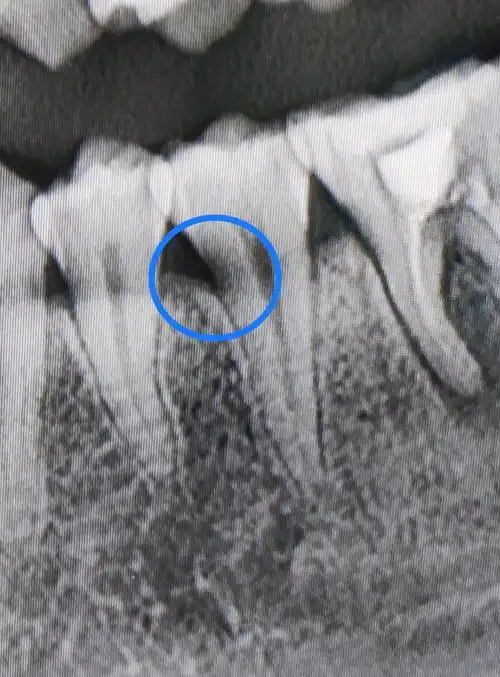

请问这是邻面龋嘛?像这样的,不疼又看不见到底在哪的医生会给补嘛?